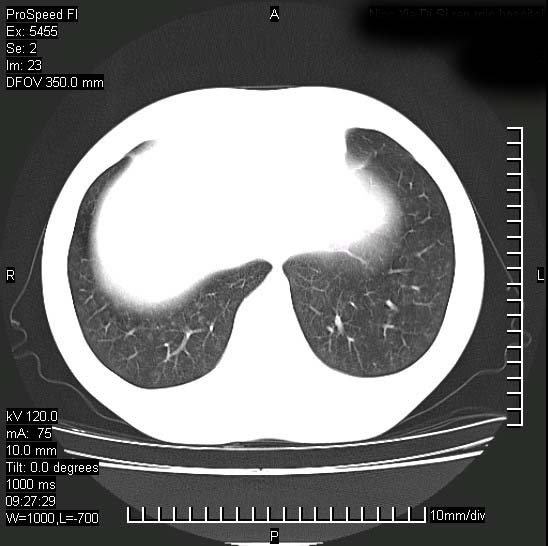

以下是引用zjzjr在2008-12-3 20:50:00的发言:[br]考虑泛细支气管肺炎,建议进一步检查除外肺出血性疾病如含铁血黄素沉着症、肺肾综合征等。

以下是引用zjzjr在2008-12-3 20:50:00的发言:[br]考虑泛细支气管肺炎,建议进一步检查除外肺出血性疾病如含铁血黄素沉着症、肺肾综合征等。

以下是引用光线在2008-12-3 20:19:00的发言:[br]双肺间质性改变。